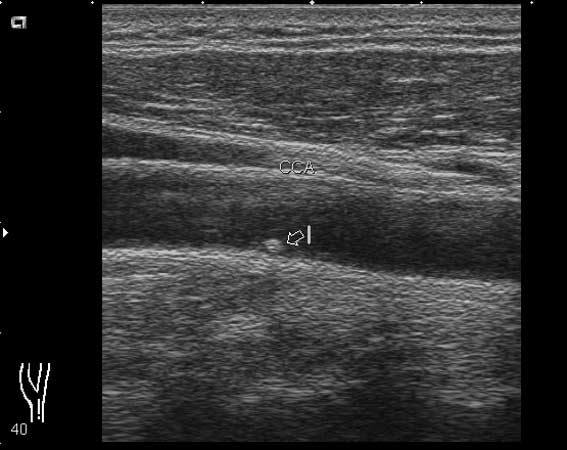

мужчина, 49 лет, при обследовании БЦА в общей сонной артерии визуализируется округлое образование 1.7х2.0 мм

ваше мнение?

Кальцинированная атеросклеротическая бляшка. Для уточнения ее истинного размера примените энергетический доплер.

локальная атеросклеротическая бяшка, которая не вызовет гемодинамически значимых изменений(если оценивать бляшку только в продольном сечении)